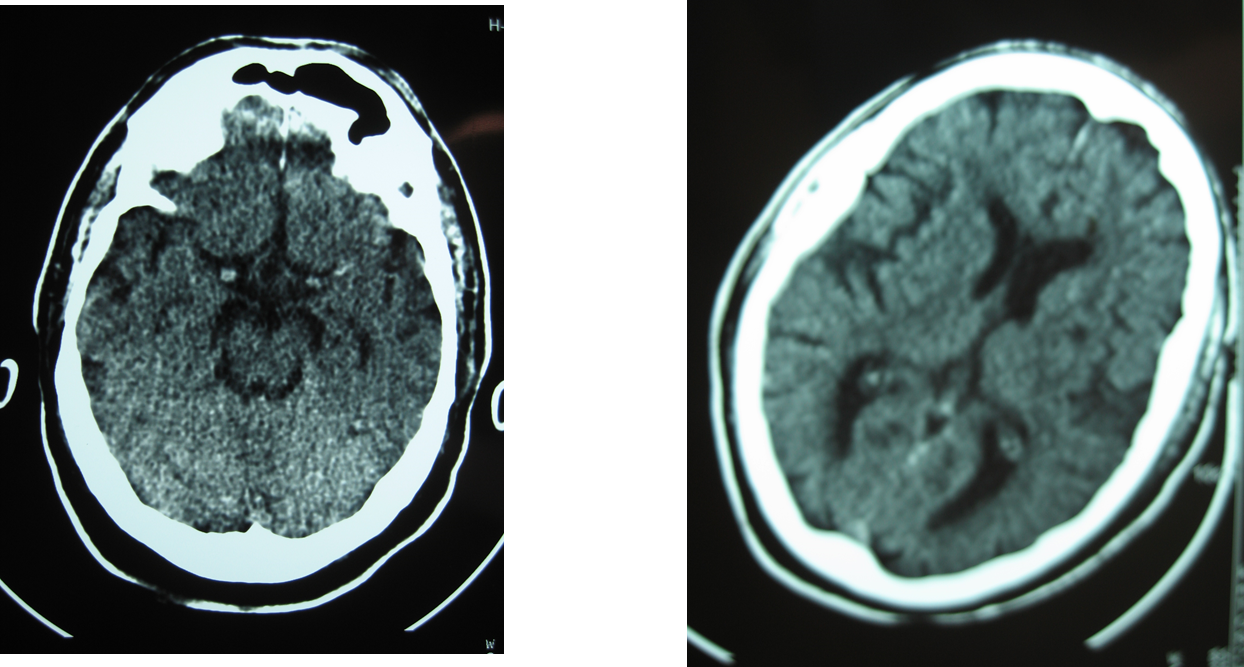

En este caso se trata de un paciente que presenta una hemorragia sintomática en la zona de isquemia con una TAC cerebral inicial normal con dos horas de evolución desde el inicio de los síntomas:

Y la TAC cerebral a las 24 horas: